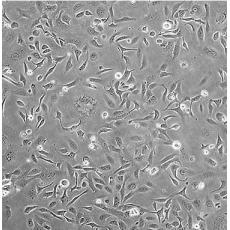

SK-OV-3 [SKOV3]

產品名稱 SK-OV-3 [SKOV3]

中文名稱 人卵巢癌細胞

組織來源 卵巢漿液性囊腺癌;腹水轉移;女性

細胞種屬 Homo sapiens, human

生長特性 adherent

培養基 McCoy's 5A+10% FBS+1% P/S

形態特征 epithelial

傳代方法 1:2-1:4

培養條件 Atmosphere: Air, 95%; CO2, 5%。Temperature: 37℃

細胞描述 SK-OV-3 cells are resistant to tumor necrosis factor and to several cytotoxic drugs including diphtheria toxin, cis-platinum and adriamycin.